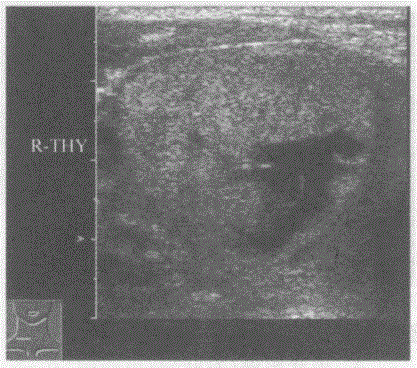

问题 临床资料:女,51岁,自述洗澡时偶然发现右颈部无痛性肿物。 临床物理检查:甲状腺右叶可扪及肿物,随吞咽活动上下移动,质软,边界清,活动度好。 超声综合描述:甲状腺右叶增大失常态,内可见8.3cm×6.3cm中等稍增强回声区,边界清晰,有完整包膜,中部可见形态不规则无回声区,CDFI:中等稍增强回声区周边可见血管绕行,内可见少许短条状动静脉血流信号。见下图及彩图。 {图1} 超声提示:

选项 A.甲状腺囊肿(右叶) B.结节性甲状腺肿 C.甲状腺癌(右叶) D.甲状腺腺瘤并囊性变(右叶)

答案 D